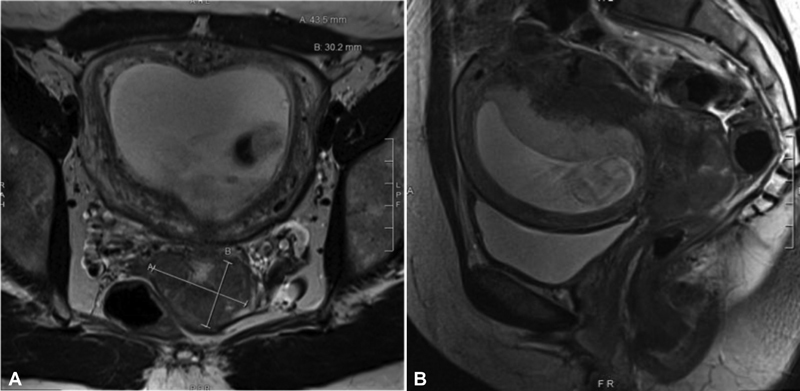

神经内分泌性小细胞宫颈癌是一种侵袭性癌症,约占所有宫颈肿瘤的 1%至 3%。在怀孕期间必须改变治疗方法,以优化母胎结局。一名 39 岁的妇女前来进行常规产前检查,发现宫颈严重异常。宫颈活检证实为小细胞癌。妊娠 19 周时,患者开始接受化疗。患者在妊娠 34 周时分娩,开始接受放射治疗。六个月后,她被诊断出患有转移性疾病,并死于癌症并发症。在妊娠期,小细胞宫颈癌的治疗方式取决于患者确诊时的妊娠年龄。虽然积极的早期治疗是首选,但铂类化疗可在妊娠后三个月开始,放疗则可推迟到分娩。妊娠并发小细胞宫颈癌需要积极治疗。在妊娠的后三个月进行化疗,并计划延迟放疗,可以优化胎儿的预后。

Neuroendocrine small cell cervical carcinoma is an aggressive cancer which accounts for approximately 1 to 3% of all cervical neoplasms. Therapy must be altered in pregnancy to optimize maternal-fetal outcomes. A 39-year-old woman presented for a routine prenatal visit and was noted to have a grossly abnormal cervix. Cervical biopsies confirmed small cell carcinoma. At 19 weeks' gestation, chemotherapy was initiated. The patient delivered at 34 weeks' gestation to initiate radiation therapy. Six months later, she was diagnosed with metastatic disease and died from cancer complications. In pregnancy, treatment modalities for small cell cervical carcinoma are based on the patient's gestational age at diagnosis. While aggressive early treatment is preferred, platinum-based chemotherapy can be initiated in the second trimester and radiation therapy delayed until delivery. Small cell cervical carcinoma complicating pregnancy requires aggressive treatment. Chemotherapy in the second trimester with planned delayed radiation therapy, may optimize fetal outcomes.